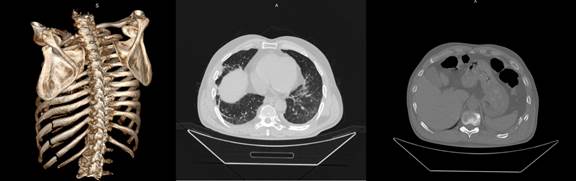

а б в

Рисунок 3. МСКТ. ТОГК.

На топограмме (а) хорошо визуализируется тотальный пневматоракс слева. На аксиальном срезе (б) кроме пневмоторакса определяется и гемоторакс (горизонтальный уровень жидкости). На фронтальном срезе можно увидеть, что воздух имеется и в плевральной полости правого легкого.